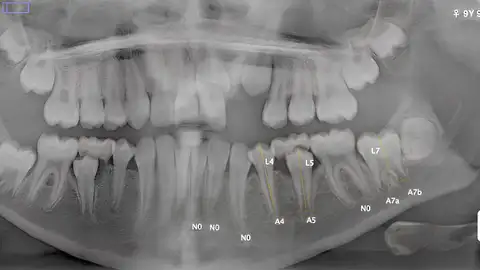

Los métodos utilizados para determinar la edad de un menor del que no existen referencias y llegan a otro país son varios. El protocolo fija que el primero en utilizarse debe ser el estudio de un hueso concreto de la mano izquierda, y en caso de dudas recurrir al estudio dental (la muela del juicio) y la clavícula. Un estudio de la Universidad de Oviedo ha concluido que lo más fiable y preciso será una combinación del estudio dental y de la mano. Nos lo han explicado en el QUÉ SE CUECE en el mundo universitario.

El profesor de Biología de Organismos y Sistemas Stefano De Luca, nos ha explicado cómo se determina la edad a día de hoy de esos menores migrantes sin referentes familiares que llegan a Europa. Ahora, porque antes se estudiaban los genitales, un dato poco preciso y que está prohibido actualmente. Estamos hablando de un dato importante, porque saber la edad legal puede ser determinantes para esos menores y es el dato que piden los jueces.

Con el uso combinado de sistemas puede determinarse la edad concreta de un menor. Y con un margen de error muy pequeño. Como hecho diferencial, han tenido acceso a datos procedentes de Sudáfrica. Stefano explica que deben seguir estudiando y ampliando la muestra a otras zonas geográficas.